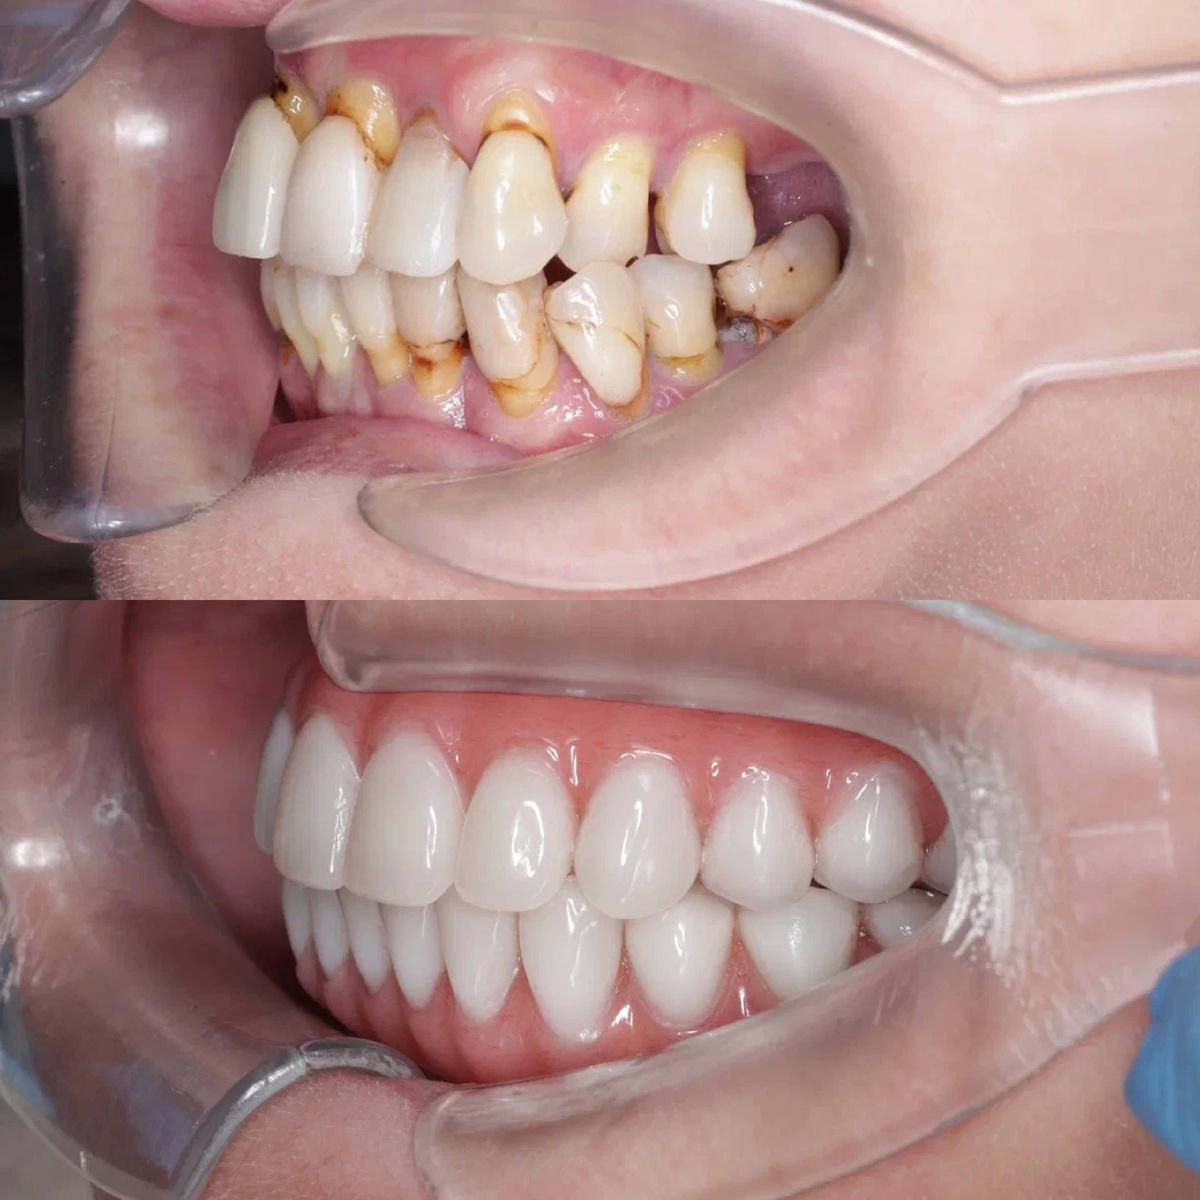

Хирург-имплантолог Барсегян Арнак Ваграмович предложил радикальное, но единственно верное решение: удалить все несостоятельные зубы и провести тотальную реабилитацию по усовершенствованному протоколу All-on-6 на обеих челюстях.

Мы не просто используем стандартные протоколы. Наша команда усовершенствовала и запатентовала методику, которая меняет правила игры. В отличие от классического подхода, где после установки имплантов вам на полгода-год ставят временный, неполноценный протез, мы фиксируем сразу постоянную, армированную конструкцию.

1. Безболезненное удаление всех разрушенных зубов.

2. Установка 6 надежных имплантов на каждую челюсть для максимальной стабильности.

3. Немедленная фиксация постоянного протеза. Никаких «времянок»!

Ольга Ивановна уехала из клиники не беззубой, не с временным решением, а с полноценными, красивыми и, главное, функциональными зубами. В тот же день она могла жевать, улыбаться и навсегда забыть о страхе, что зубы могут выпасть или заболеть во время еды.